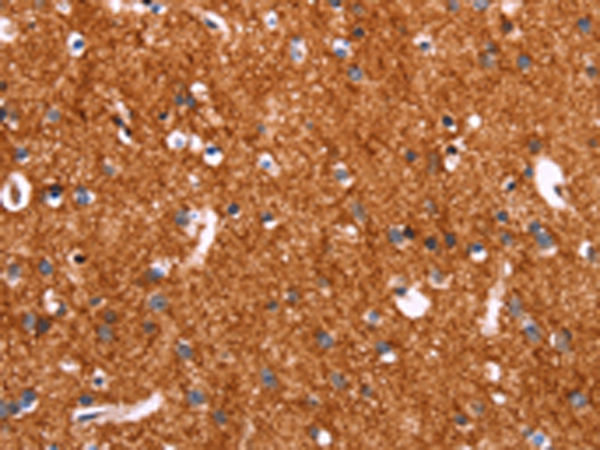

分类: 科研抗体货号: P04889别名: GAT1; GABATR; GABATHG应用: WB,IHC反应种属: Human, Mouse, Rat